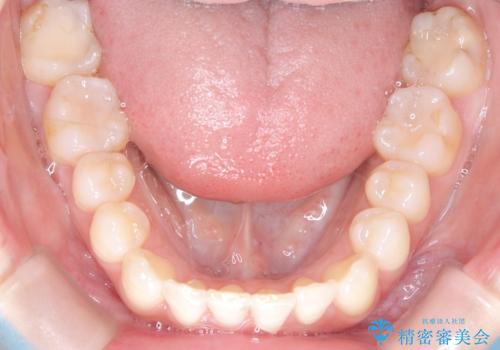

インビザラインで整えた前歯の歯並び

- 患者様は、上下前歯の歯列不正(ガタガタ)を主訴としてご来院されました。治療計画として、透明なマウスピース型矯正装置「インビザライン」を使用し、約2年の期間を見込んで前歯部の歯列を整える方針を立てました。特に下顎前歯に歯肉退縮のリスクがあるため、治療中にIPR(インタープロキシマルリダクション)を行い、歯間を適切に削ることで、過度な圧力を避け、歯肉退縮を防ぎながら配列を進めました。治療は慎重に進め、最終的にきれいで整った前歯の歯並びを目指しました。

インビザラインによる矯正治療は、患者様自身が装着するマウスピース型の装置を使用するため、装着時間の徹底が重要です。特に、下顎前歯の歯肉退縮を避けるため、IPRを施すことで歯間スペースを確保し、歯肉にかかる負担を減らしました。この方法により、歯並びを整えながらも歯肉の健康を保つことができます。治療期間中は定期的にチェックを行い、歯肉の状態や歯の動きを慎重に確認しました。また、治療後はリテーナーを装着して歯並びを維持し、安定させました。